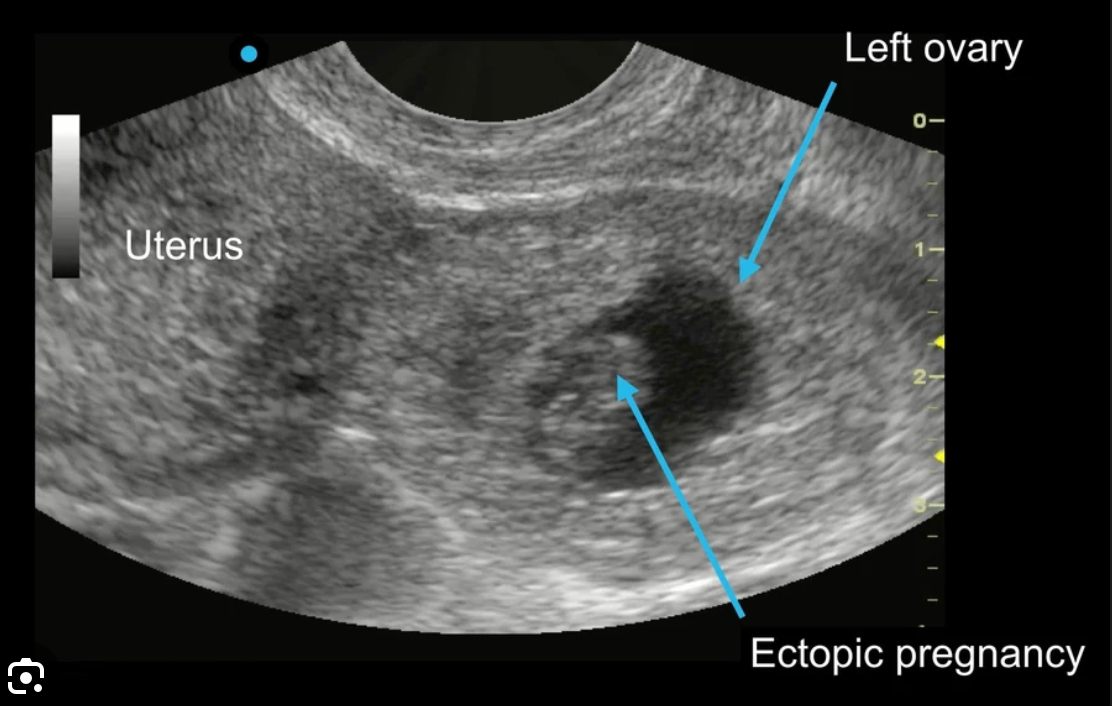

- Confirmation of pregnancy and its location, specifically to exclude ectopic pregnancy and gestational trophoblastic disease.

- Transvaginal ultrasound: Provides detailed images of the uterus, ovaries, and early pregnancy structures.

- Transabdominal ultrasound: Used for broader overviews of the abdominal cavity and later in pregnancy to assess fetal growth, placental location, and amniotic fluid volume.